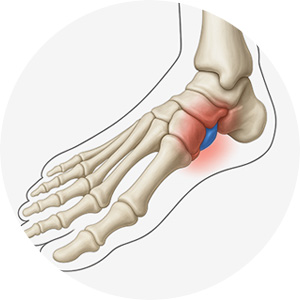

엄지발가락이 원래 위치에서 새끼발가락 방향으로 휘어지면서 통증을 유발하는 질환입니다.

엄지발가락이 둘째발가락 쪽으로 휘어짐

엄지발가락 관절이 안쪽으로 돌출

돌출된 부위에 굳은살이 생기고 통증 발생

걸을 때 불편함

발 모양의 변형